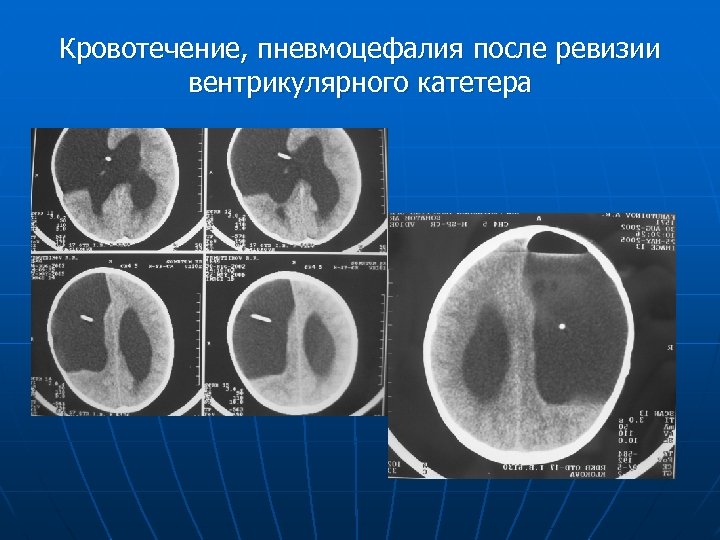

Кровотечение, пневмоцефалия после ревизии вентрикулярного катетера